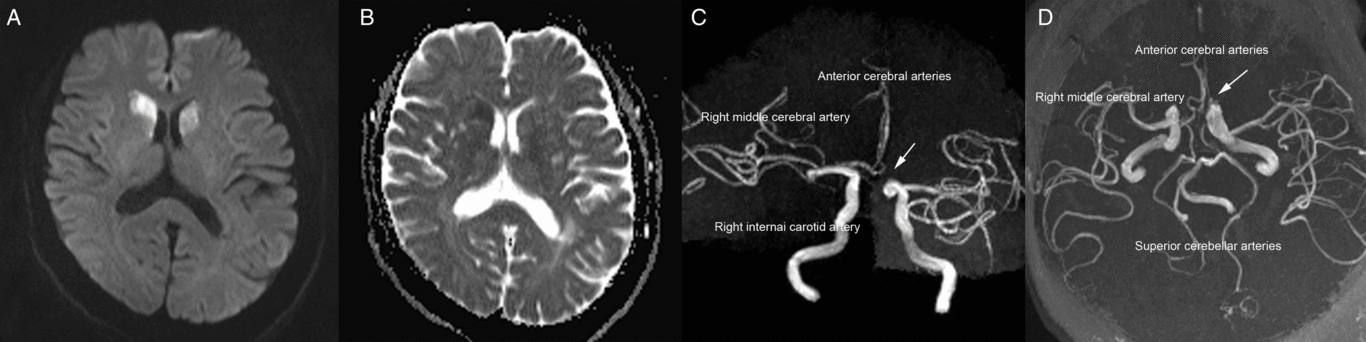

A 60-year-old woman was admitted to our emergency room with acute-onset chorea of all four extremities (see video in supplementary material). Her medical history was unremarkable apart from hypertension. A neurological examination revealed no abnormalities apart from involuntary movements. Brain magnetic resonance imaging showed acute bilateral infarctions in the head of the caudate nucleus (Figure 1A and B). Magnetic resonance angiography revealed that both anterior cerebral arteries (ACAs) originated from the right internal carotid artery (Figure 1C and D). We started administering oral antiplatelets (aspirin at 100 mg/d and clopidogrel at 75 mg/d) and oral atorvastatin (40 mg/d) for 21 days after the final diagnosis, and the patient’s chorea signs spontaneously improved. The aspirin and atorvastatin continued to be administered after discharge. At the 6-month follow-up assessment, the patient reported no residual symptoms.

Figure 1: (A) Diffusion-weighted imaging conducted 2 days after symptoms onset revealed a high-intensity signal in the bilateral head of the caudate nucleus. (B) The apparent diffusion coefficient values within the bilateral head of the caudate nucleus were low. (C and D) Magnetic resonance angiography revealed variations in the anterior cerebral arteries (arrows).